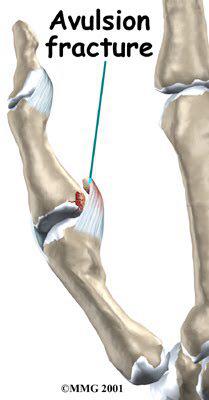

출처 MMG